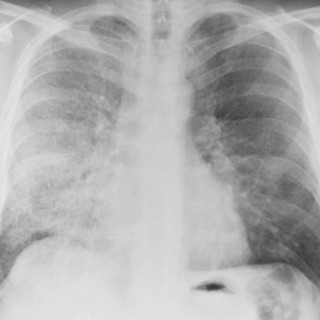

En 40 år gammel kvinne ble innlagt i medisinsk avdeling til utredning for anemi (1). Hun hadde tidligere vært frisk, men hadde de siste månedene før innleggelsen følt seg tiltakende slapp og tungpustet. I en periode hadde hun hatt rikelige og langvarige menstruasjoner. Av egen lege hadde hun fått jerntabletter, men hadde likevel Hb 6,8 g/100 ml. Ved innleggelsen var pasienten i noe redusert allmenntilstand, blek, men med uanstrengt respirasjon. Organstatus var normal, bortsett fra at man mente å kunne palpere uterus. Blodprøvene viste følgende verdier: Hb 6,5 g/100 ml, leukocytter 6,0 · 10⁹/l...